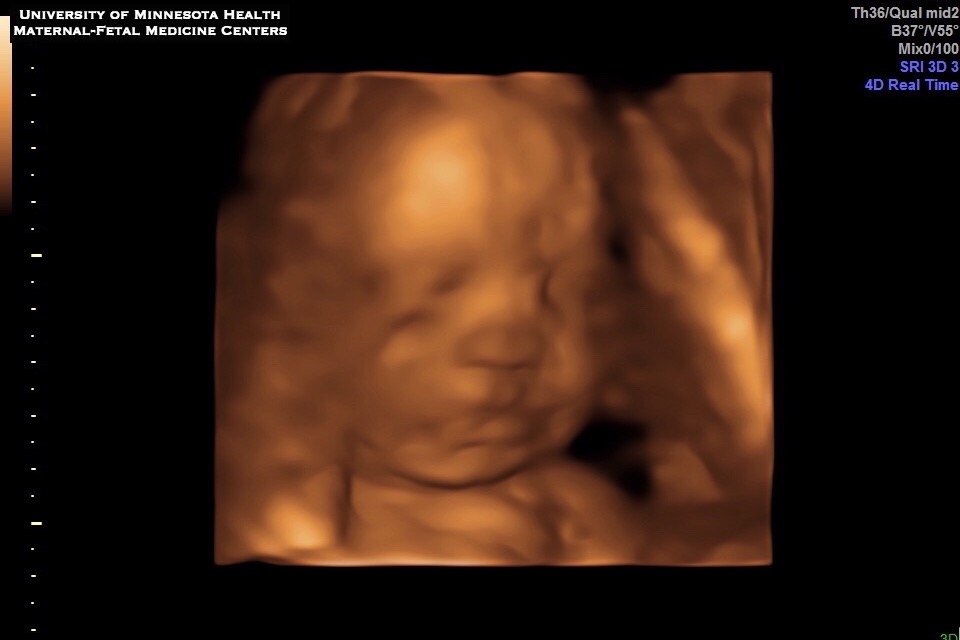

They went in for their 20 week ultrasound and got some news that was very upsetting but at the same time a blessing to find early. Nikki was diagnosed with Velamentous Cord Insertion, low lying Placenta and Vasa Previa, a rare condition with only 1 in 2500 births.

Adeline Esme made her grand entrance on the morning of May 23rd and only weighed 3 lbs 14 oz and went directly to the NICU after she was born and has been there since. She is currently 10 days old and may be small but she is mighty and strong!